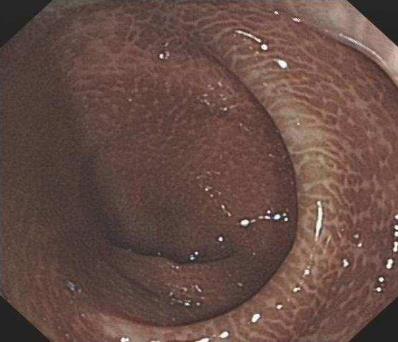

“武漢漢西博仕肛腸醫院”專家說,有些便秘患者有長期的清茶,這會引起依賴性。清茶雖然能使人順利清腸一段時間,但也會產生不良的后果,甚至導致結腸變黑。通常理解,結腸是黑色的,大腸的粘膜變黑,這是粘膜色素沉著病的表現。黑變病還能引起大腸其他疾病,不容忽視。